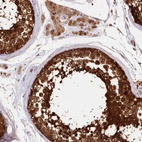

Immunohistochemical staining of human testis shows strong cytoplasmic and nuclear positivity in seminiferous tubules.